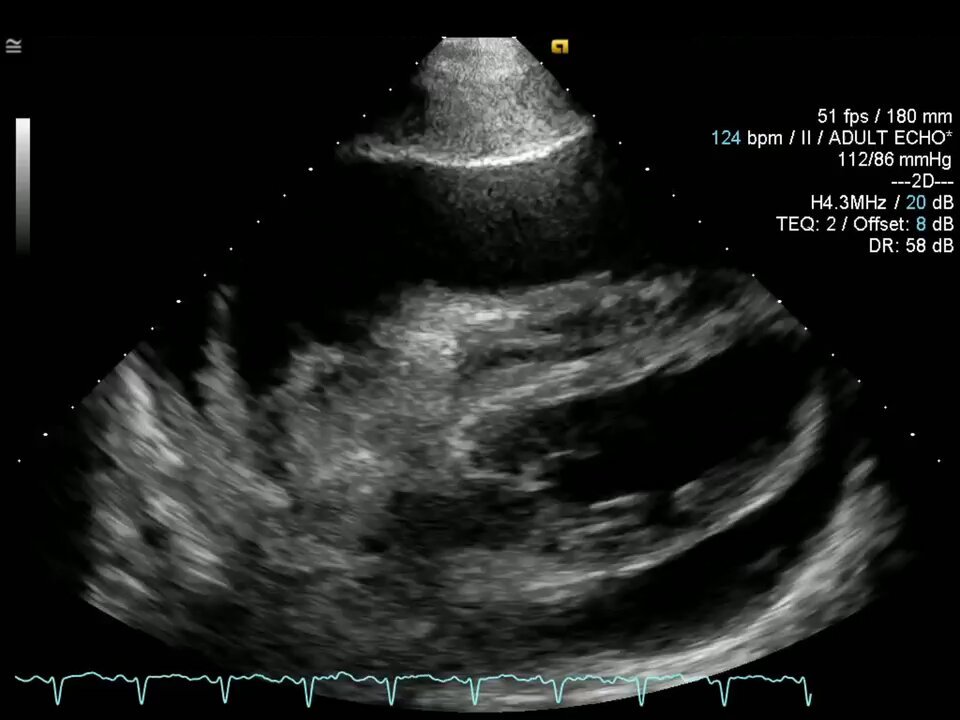

Interesting sequence of events - from Muchmore, et al. J Am Coll Cardiol Case Rep. 2025 Aug, 30 (25) . doi - 10.1016/j.jaccas.2025.104821 #POCUS #FOAMed #FOAMcc Image 1️⃣ - Initial #echocardiogram showing large, circumferential pericardial effusion, right atrial collapse, and…